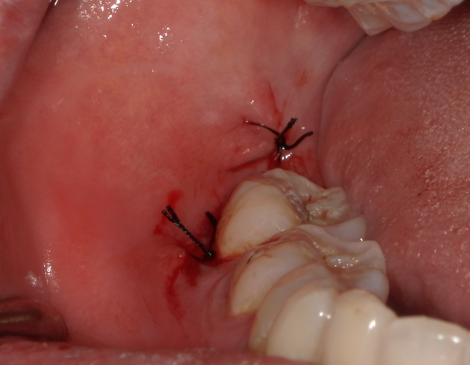

为了取出它,医生往往需要切开牙龈、去除部分骨头,甚至将牙齿切割成小块分次取出。这种手术创口较大,术后容易出血,且暴露的伤口更容易感染。

拔牙后,开放的创口可能持续渗血。缝合能将两侧牙龈组织拉紧贴合,压迫血管末端,减少出血量。尤其是阻生智齿周围血供丰富,缝合是预防术后出血的关键步骤。

口腔是充满细菌的环境,敞开的伤口容易成为细菌的“入口”。缝合后,牙龈组织紧密闭合,形成物理屏障,减少食物残渣和细菌侵入深层组织的风险。

干槽症(拔牙后骨面暴露引发的剧痛)是阻生智齿拔除后的常见并发症。缝合能将牙龈覆盖在骨创表面,帮助血凝块稳定形成,为组织再生提供保护。

通过缝合对齐牙龈边缘,伤口愈合时无需从底部“爬坡式”生长,能更快闭合,缩短恢复时间(通常从2-3周缩短至1-2周)。

不可吸收线(如丝线):需术后7-10天拆除,稳定性更强,便于医生观察愈合情况。